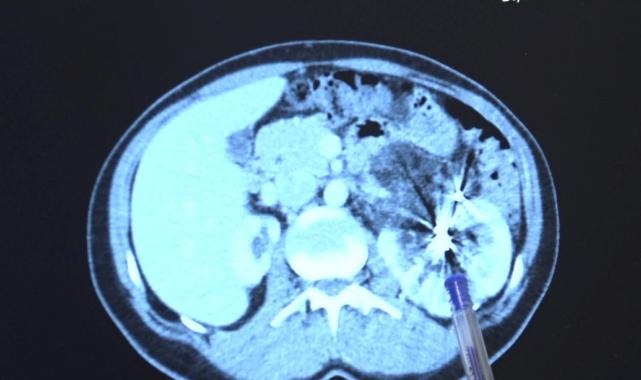

Yıllar sonra tekrar MR çektiren hastanın tek böbreğinde bu sefer bir kitle olduğu görüldü.

Zorlu bir ameliyatı başarıyla tamamlayan Bursa Medicana Hastanesi Üroloji Uzmanı Doç. Dr. Ahmet Şahan, hastanın durumunun şuan iyi olduğunu belirterek, “Nurcan Hanım 35 yaşında bize İzmir'den geldi. Doğuştan tek böbrekli bir böbreği küçük olduğu için işlevsiz durumda. Sağlam böbreğinde ise 2016'da tanısı konmuş giderek büyüyen iyi huylu "anjiomyolipomu" denilen 12 santimetre boyutunda bir kitlesi var.

Bu kitle artık böbreğin damarlarını içerisine almış komplike bir kitle durumunda. Hastaya iki kez anjioembolizasyon tedavisi uygulanmış fakat başarısız olduğu için kitle büyümeye devam etmiş. Kadınlarda 4 santimetreden büyük anjiomyolipomular kendiliğinden kanayarak yaşamı tehlike altına attığı için bu kitlelerin alınması gerekiyor.

Tek böbrekli olunan durumlarda böbreğin tamamen alınması durumu da söz konusu olabiliyor. Bu riske girmemek için çoğu merkez de embolizasyona başvurmuş. Hasta bize geldiğinde bu işi yapabileceğimizi söyledik.

2 saat süren kapalı bir ameliyatla kitleyi tamamen çıkardık ve hastamızı 3 gün içerisinde taburcu ettik. Hastamızın değerli şuan iyi durumda. Hastamızı diyalizden kurtarıp kapalı bir ameliyatla sağlığına kavuşturabildiğimiz için çok mutluyuz” dedi.